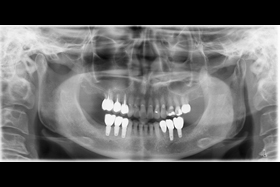

治療前全口x光片、口內照片

治療後全口X光片